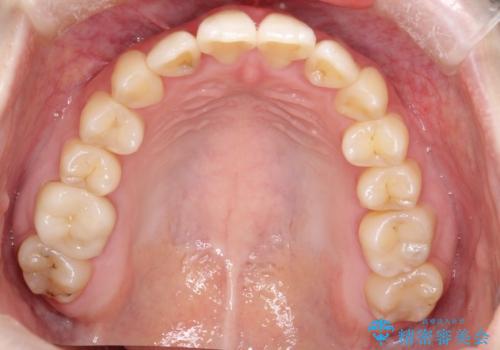

前歯が前後反対にかんでいる インビザラインによる矯正

しっかりとマウスピースを使用していただけたので、順調に治療を終えることができました。

- 前歯のがたつきを気にされて来院されました。

上顎の前から二番目の歯が内側に入り込んでおり、前後反対にかんでいる状態でした。

歯と歯の間にわずかに隙間を作り並べる計画としました。